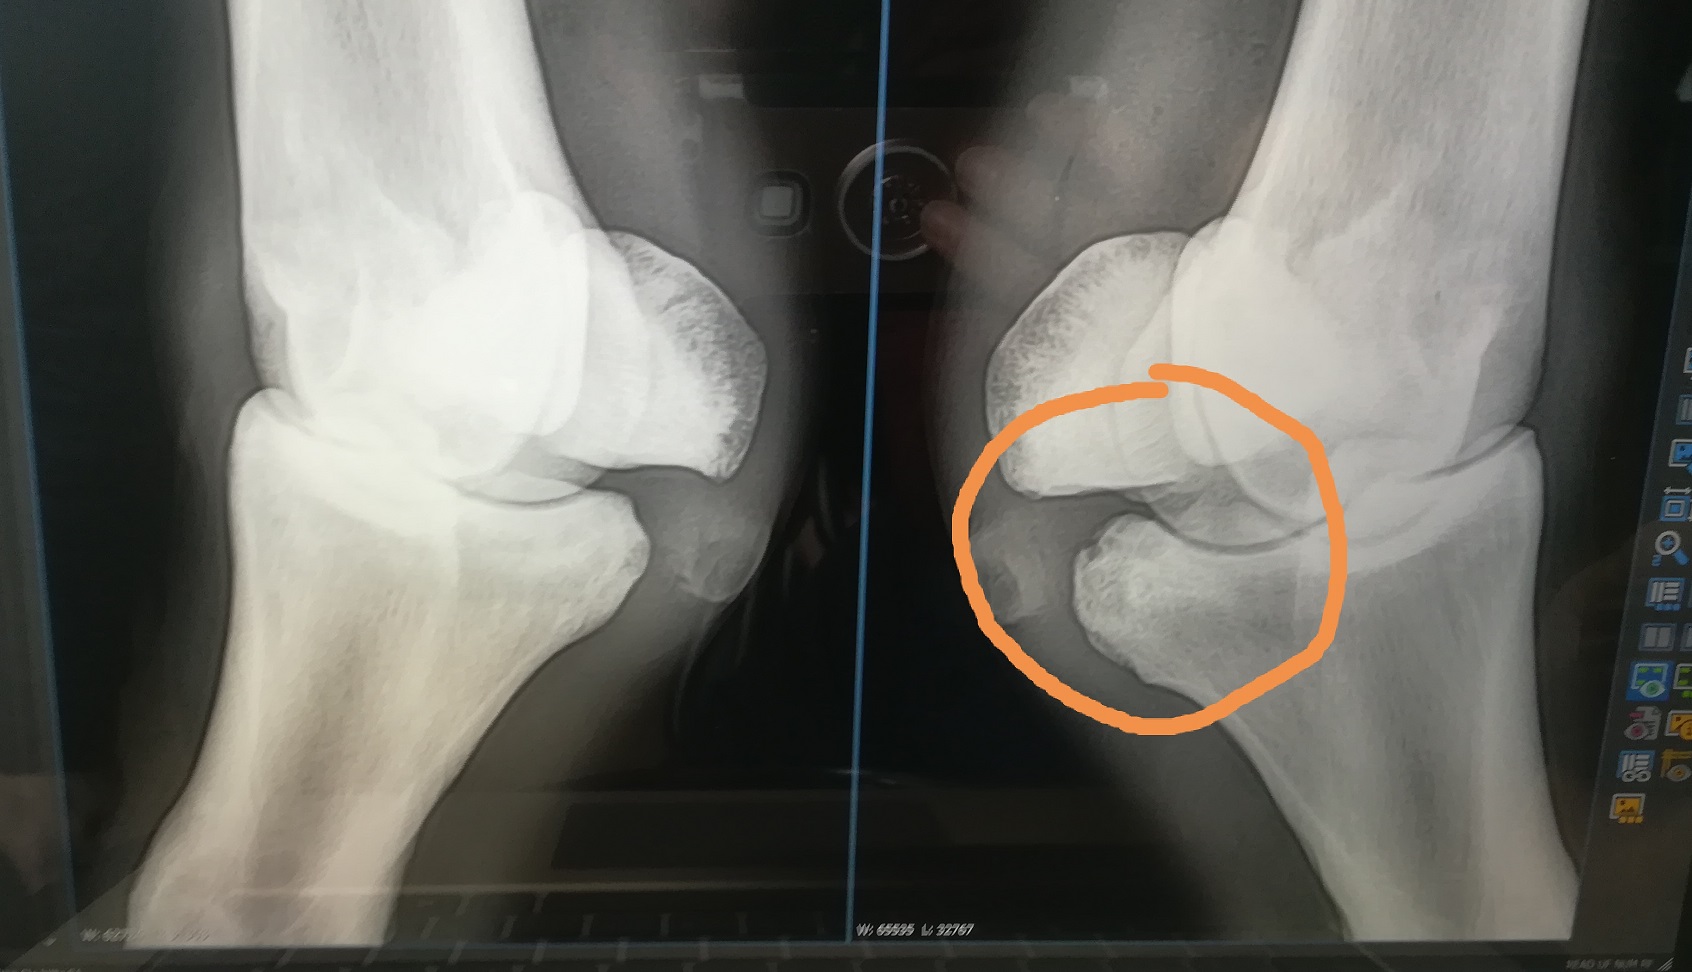

nach 17 Monaten tolles reiten bei mir und meinem vierbeinigen Freund, haben wir eine neue Baustelle: Knochenzubildung bzw Arthrose im Fesselgelenk außen am Hinterbein ;( inkl. Fesselgelenksentzündung , was wohl ohne dem nicht geht :cursing: naja, da ich bei schonmal mit Vitalpilzen ganz gut gefahren bin (Sehnenverletzung) wollte ich mal horchen, was eure Erfahrungen zu diesem Fall sind. Einer sagt: Vitalpilze - der andere meint: MSM, Glucosamin, Chondroitinsulfat und Hyaloron....:/ ich bin völlig durcheinander. Nächste Woche bekommt meiner Pferd eine Eigenbluttherapie mit Cortison und Hyaloron ins Gelenk gespritzt ..aber was kann ich füttern um ihn von innen heraus und auch langfristig zu unterstützen?! Habt ihr einen Tipp und Erfahrungen?!?

~ TA mit Röntgen am 26.12.2020 - Fesselgelenk etwas mit Flüssigkeit gefüllt und (evtl.) beginnende Arthrose

Vor knapp zwei Wochen fing er allerdings an, leicht vorne auf einem Bein zu lahmen. Mal ja - mal nein...da es nicht besser wurde und er weder eine Schwellung oder eine warme Stelle am Bein hatte (was immer für eine Entzündung etc. sprechen würde), rief ich den TA an und wir haben das Bein geröngt - Ergebnis: beginnende Arthrose im Fesselgelenk. Aber noch so minimal, dass man es nur aus einem bestimmten geröngten Winkel sehen/erkennen/erahnen kann.

Die TA sagte auch noch, ich solle das mit der Arthrose nicht so ernst nehmen - es sei wirklich nur mini-minimalst zu erkennen oder zu erahnen. Wir könnten in einem halben Jahr ein Vergleichs-Röntgenbild machen und dann mal schauen, ob da wirklich was ist....